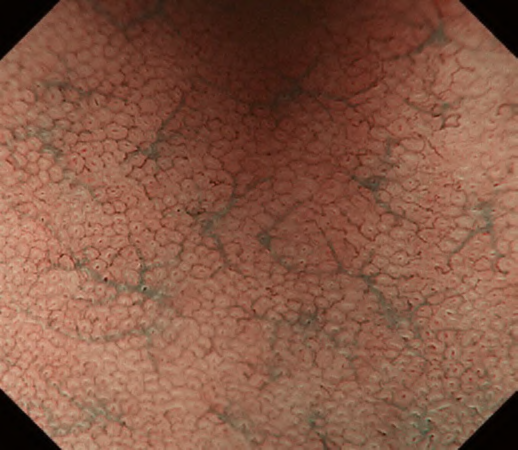

The VS classification system developed by the author (Kenshi Yao) [1] is the most widely accepted diagnostic system for magnifying narrowband imaging (M-NBI) of the stomach [2]. The VS classification system employs anatomical terms as endoscopic markers for analysis. Anatomical components visualized using M-NBI were divided into microvascular (MV) and microsurface (MS) patterns. As shown in . Fig. 1a–c, the subepithelial capillary and collecting venule were visualized for MV pattern, while the marginal crypt epithelium (MCE), crypt opening (CO), and intervening part (IP) between the crypts were identified for the MS pattern. In addition, in terms of the pathological status, the light blue crest [3] and white opaque substance [4] can be markers for microsurface patterns.

According to the morphology of the anatomical components, the MV and MS patterns were classified as regular, irregular, or absent (. Fig. 2). In principle, the MV and MS patterns must be determined separately.